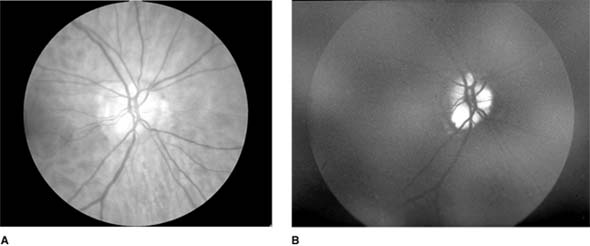

Figure 14-25

Figure 14-25: Optic nerve head drusen (A) exhibiting autofluorescence (B).